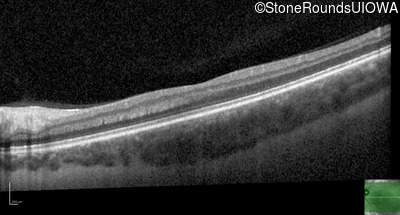

Optical Coherence Tomography - Right - Count Fingers 1'

Exemplar / OCT Stack

Optical Coherence Tomography - Left - 20/1000